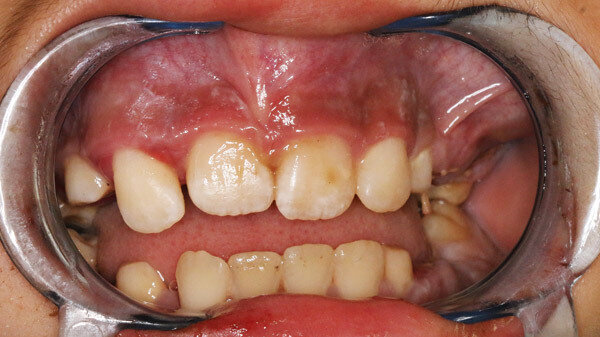

Die Anamnese war aufgrund der Sprachbarriere erschwert, seitens der Eltern hieß es, der Zustand bestehe schon seit einigen Tagen. Es wurden keine Vorerkrankungen und keine feste Medikation angegeben. Die klinische Untersuchung zeigte eine weiche, wenig schmerzhafte Schwellung im linken Oberkiefervestibulum (Abbildung 1).

Die Zähne 64, 65 und 75 waren kariös zerstört. Weiterhin wurden bei der eingehenden Untersuchung zweit- bis drittgradige Lockerungen an sämtlichen Milchmolaren des Oberkiefers, zweitgradige Lockerungen der Milchmolaren im Unterkiefer sowie erst- bis zweitgradige Lockerungen der bleibenden Inzisivi am Oberkiefer festgestellt. Die Mundschleimhaut war intakt, die Sensibilität im Gesichtsbereich und die Mundöffnung mit 33 mm Schneidkantendistanz waren unauffällig. Zervikal konnten beidseits mehrere vergrößerte Lymphknoten palpiert werden, die übrige körperliche Untersuchung zeigte keine Auffälligkeiten.